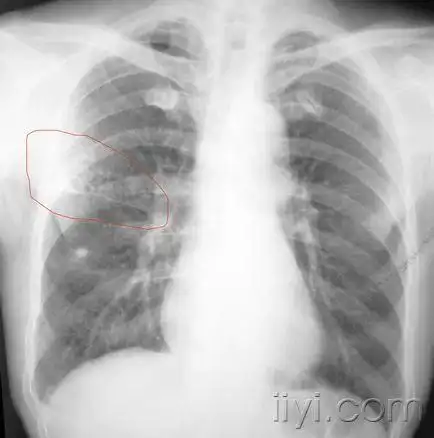

右肺蜂窝影